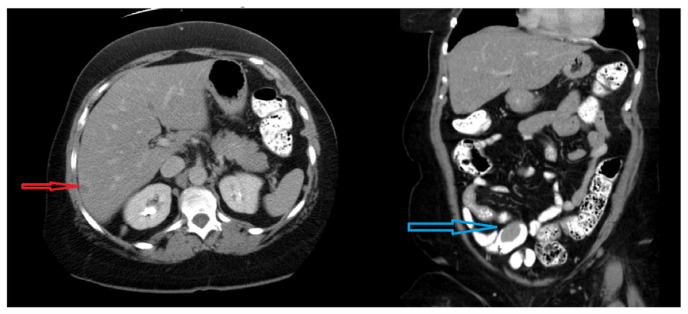

Carcinoid tumors are rare, slow-growing neoplasms of neuroendocrine origin commonly affecting the gastrointestinal or respiratory system. They metastasize to lymph nodes and the liver based on their lymphatic and venous drainage of their tissue of origin. Metastasis to the heart is exceedingly rare accounting for <2 % of cases. Exceedingly rare is the incidental detection of cardiac carcinoid metastasis as the initial presentation of carcinoid syndrome. Here, we describe a case of metastatic cardiac carcinoid detected during a routine echocardiogram done for evaluation of a systolic murmur.